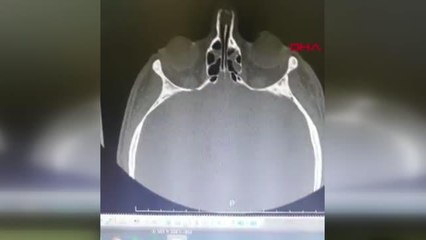

Samsun'da hasta yakını, hastanede doktora saldırarak burnunu kırdı. Doktorun hayati tehlikesi bulunuyor. brpSamsun'da hasta yakını, hastanede doktora saldırarak burnunu kırdı. Edinilen bilgiye göre, 2 yaşındaki M.D.İ., adlı kız çocuğu evlerindeki salıncaktan düşerek yaralandı. Özel bir hastaneye kaldırılan M.D.İ. acil serviste tedavi altına alındı. Acil serviste görevli Dr. Ahmet Kurt, çocuğun çekilen tomografisini inceleyeceği sırada çocuğun babası H.İ. ile kardeşi Ş.İ.'nin saldırısına uğradı. Doktorun odasındaki bilgisayar yere düşüp zarar görürken, Dr. Kurt saldırıyı yara almadan atlattı. Hastaneye polis sevk edildi. Ağır yaralı olan çocuğun tomoğrafi filmini incelemek için başka odaya giden Dr. Ahmet Kurt, çocuğun beyin kanaması geçirdiğini tespit edince acil olarak Samsun Ondokuz Mayıs Üniversitesi Tıp Fakültesi Hastanesi'ne sevkine karar verdi.br br hbrlr1.